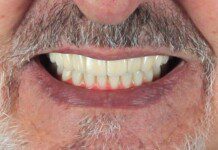

Frontal view of the implant temporary in the mouth. This temporary will stay in place for 2 more months as the bone and soft tissue remodel after the extractions.